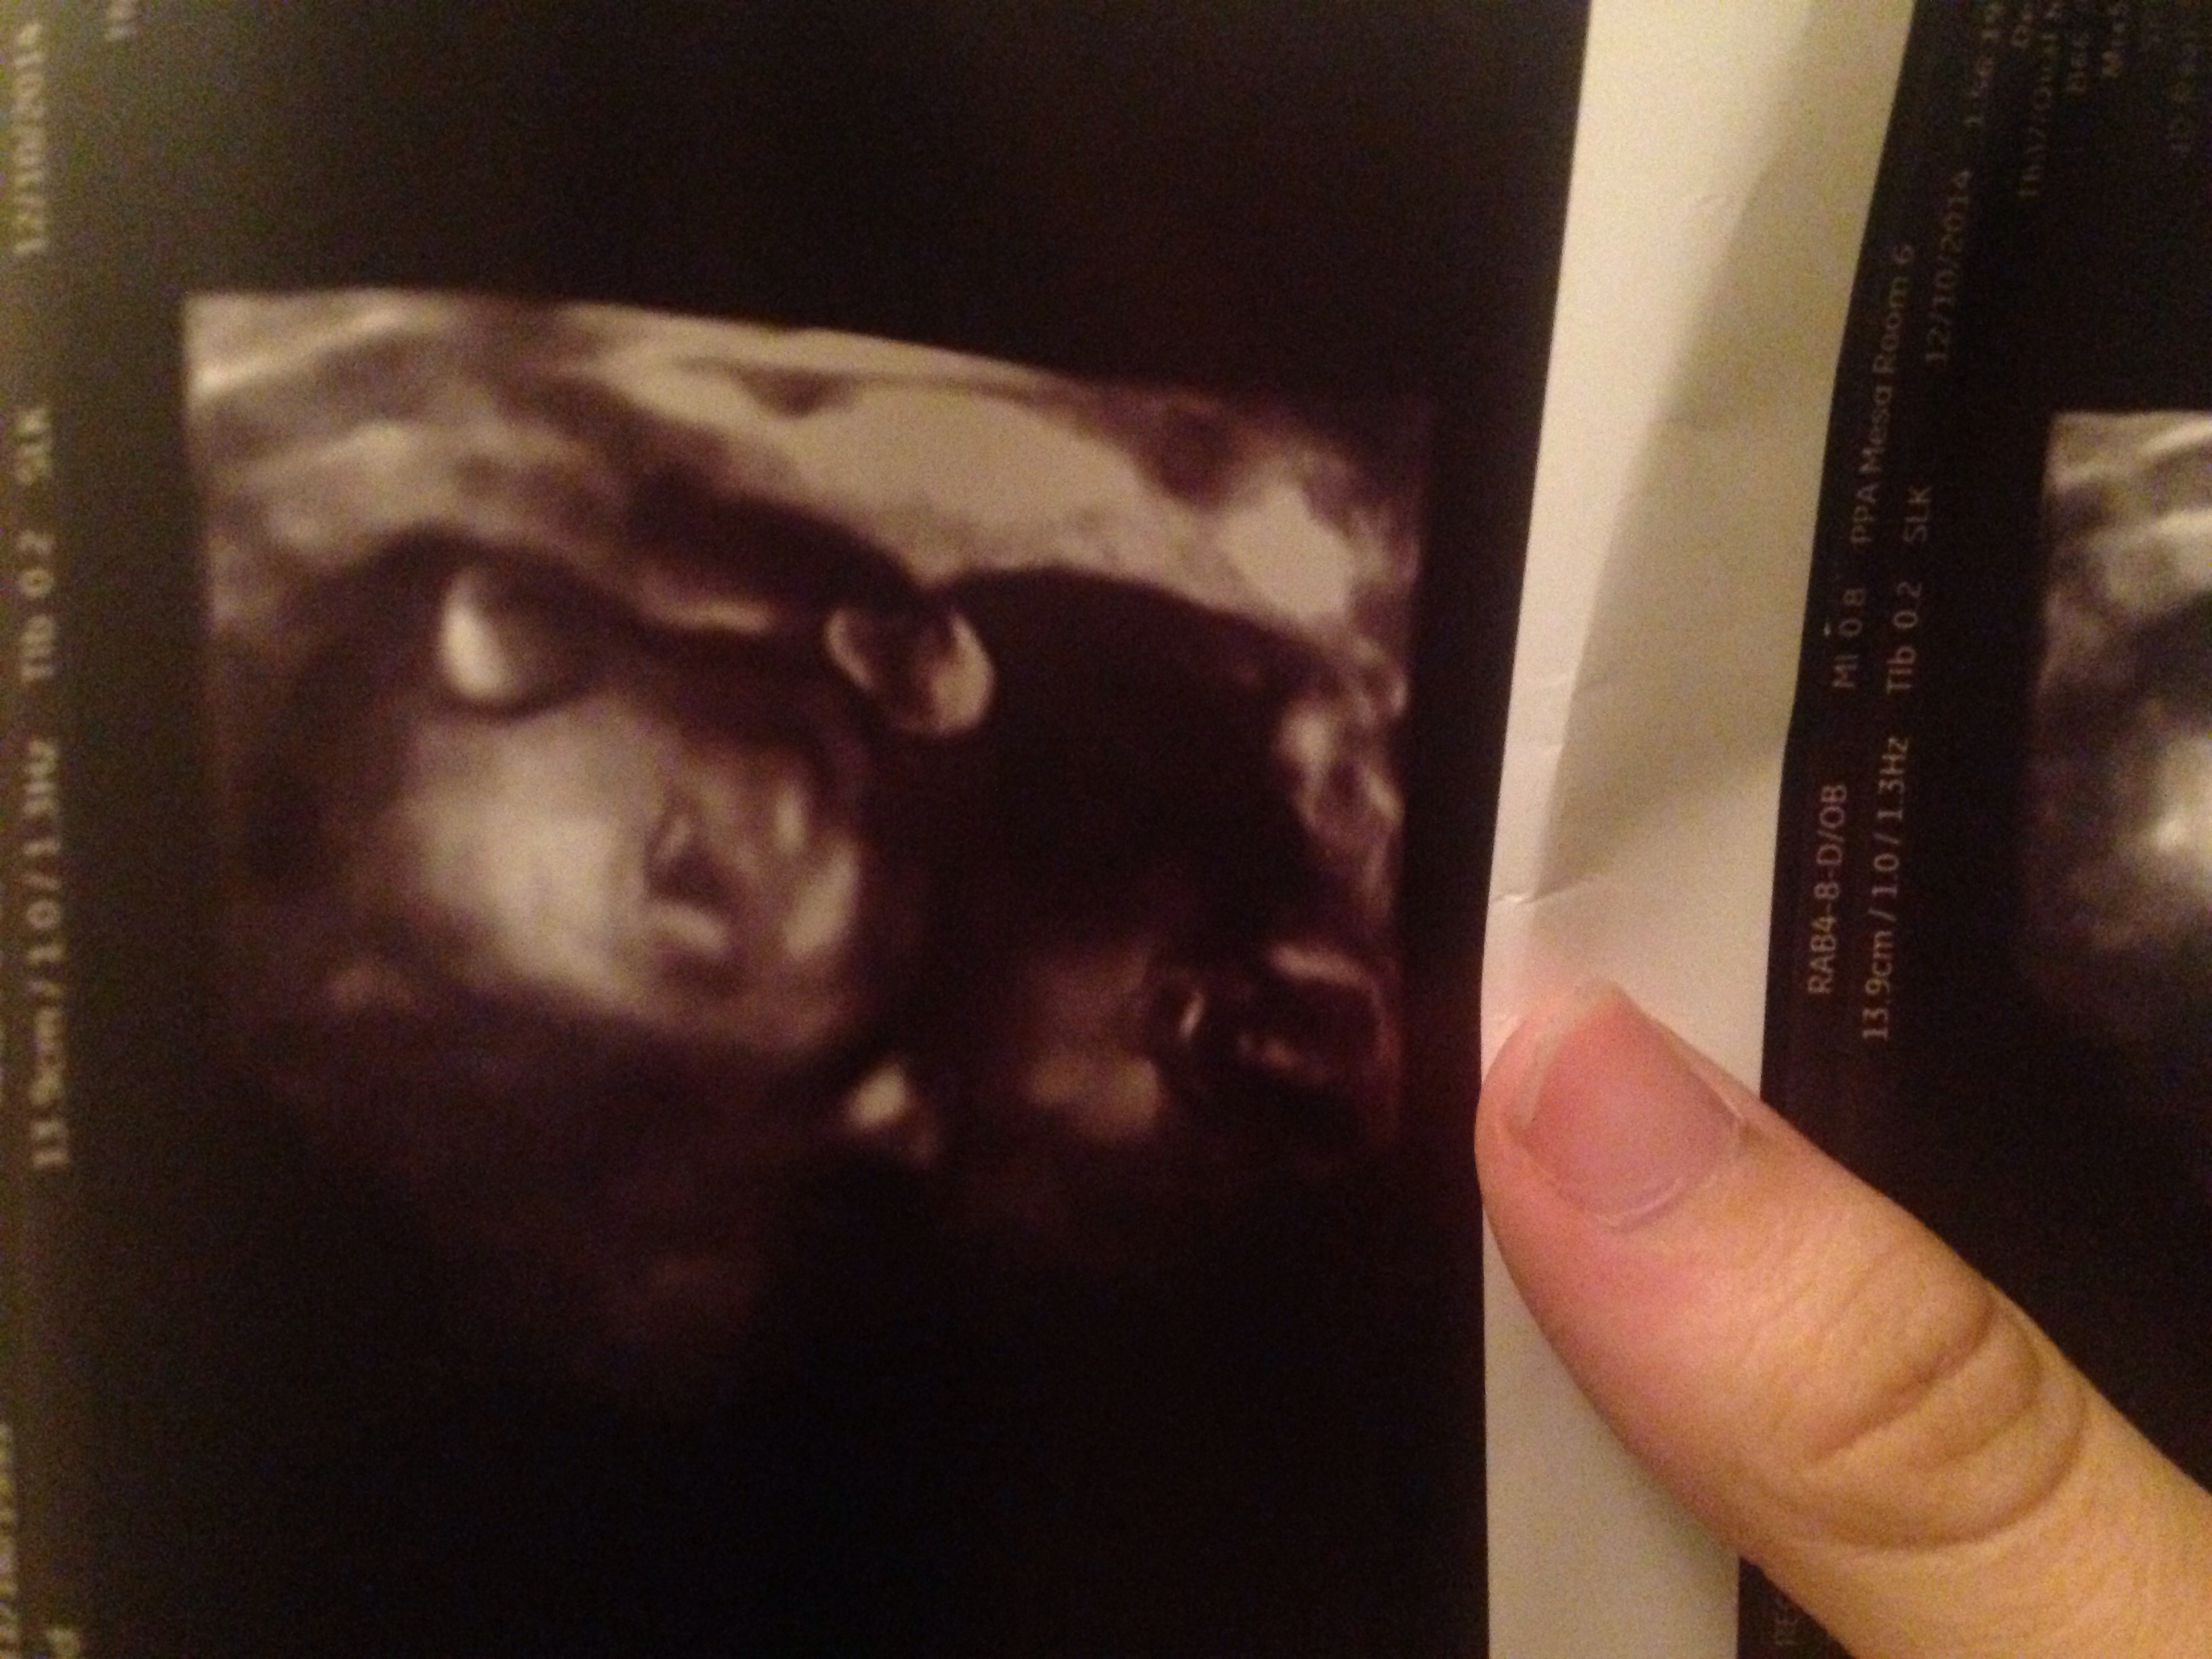

I took this Friday for some family (21w3d) and today I'm 22wks! I wonder why there is not ticker change on Wednesdays...maybe I'll make on next week! You all look fantastic!